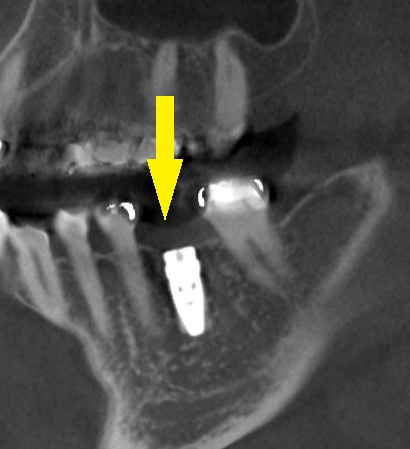

抜歯後4か月でCTを撮影してみると、骨の再生はありますが、一部は吸収されたままで、欠損が残っていました(下の写真2段目右)。

そこで、頬側に人工骨を使用した骨造成術を併用してのインプラント埋入を行なう計画とし、本日手術を施行しました。

下の写真3段目が手術後のCTとなります。